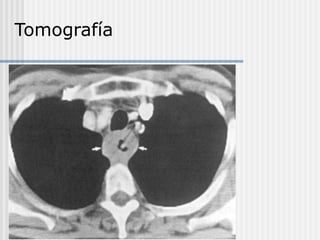

7. TC de tórax y abdomen alto

 Se valora la infiltración a órganos adyacentes y

gánglios mediastínicos.

 Detecta metástasis hepáticas y pulmonares.

 Orienta acerca de la resecabilidad del tumor.

Estadificación Preoperatoria.

 Penetración ( T )

 Ecoendoscopía (EUS)

 TAC

 Ganglios Linfáticos Regionales ( N )

 Ecoendoscopia (EUS)

 Metástasis a distancia (M)

 Pet Scan

Tomografía